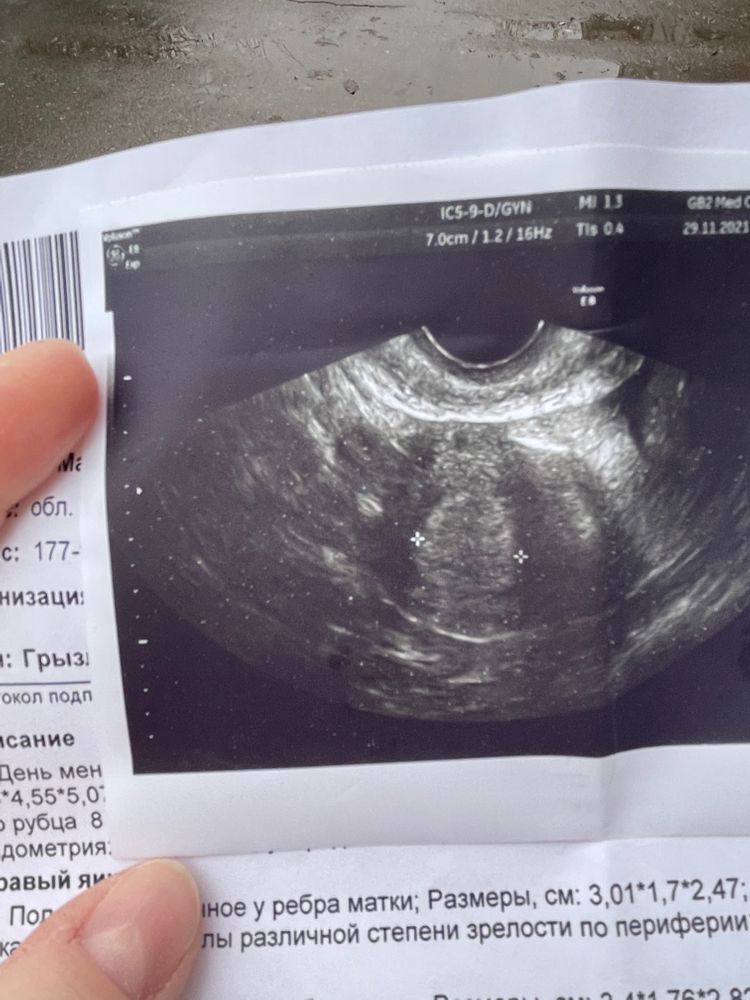

Ничего нет на УЗИ. Гиперплазия (ГПЭ) всегда ставится, когда месячные должны прийти, но еще не пришли, там дохрена эндометрия нарастает.  Тут либо анализы на гормоны сдавать, либо подождать еще, возможно у Вас перестройка организма

У вас написано ГПЭ- это Гиперпластические процессы эндометрия (гиперплазия, полипы)